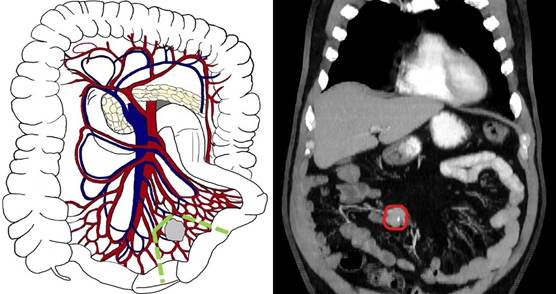

Первый тип - локализация конгломерата вблизи стенки кишки с поражением только прямых сосудов, что соответствует концепции I уровня по классификации Ohrvall. В данном случае целесообразно выполнение перевязки прямых сосудов с пересечением аркады по границе поражения и единичных радиальных сосудов выше метастатического узла и резекции вовлечённой части тонкой кишки с клиновидной резекцией брыжейки (рис. 1).

Рис. 1. Первый тип (уровень I) - локализация конгломерата пораженных лимфатических узлов в непосредственной близости к кишечнику с вовлечением терминальных сосудистых ветвей